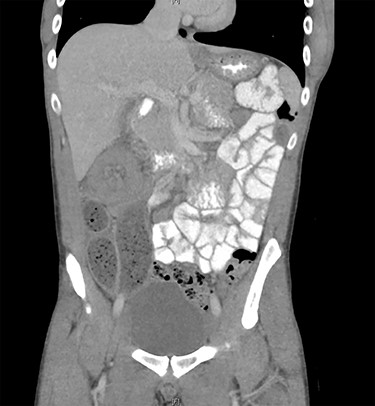

Due to diagnostic uncertainty, the patient underwent a computed tomography (CT) of the abdomen and pelvis with intravenous and oral contrast, which demonstrated ileo-colic intussusception, a distended ileum and no other features of bowel obstruction. Coronal and axial views of the CT scan showing the ileocolic intussusception are displayed in Figs 1 and 2, respectively.

CT of the abdomen and pelvis with coronal view showing ileo-colic intussusception.